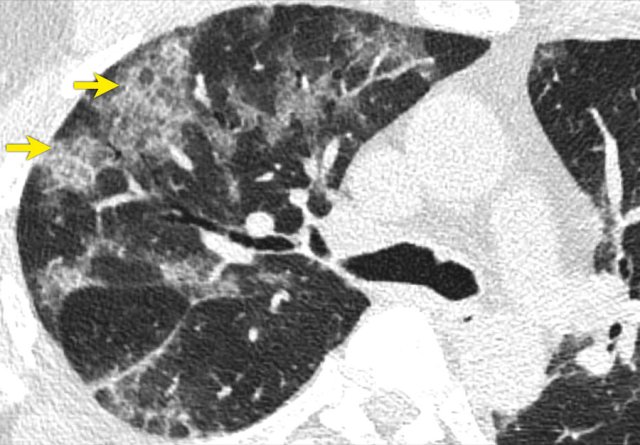

These images are of a 49 year old male with fever, cough and a low saturation.

The images show:

• Bilateral areas of GGO.

The ground glass density is more pronounced

• Fibrotic bands (arrows).

• Dilated vessels in affected area (circle).

Based on the CT-findings COVID-19 infection was assumed to be highly likely - late phase.